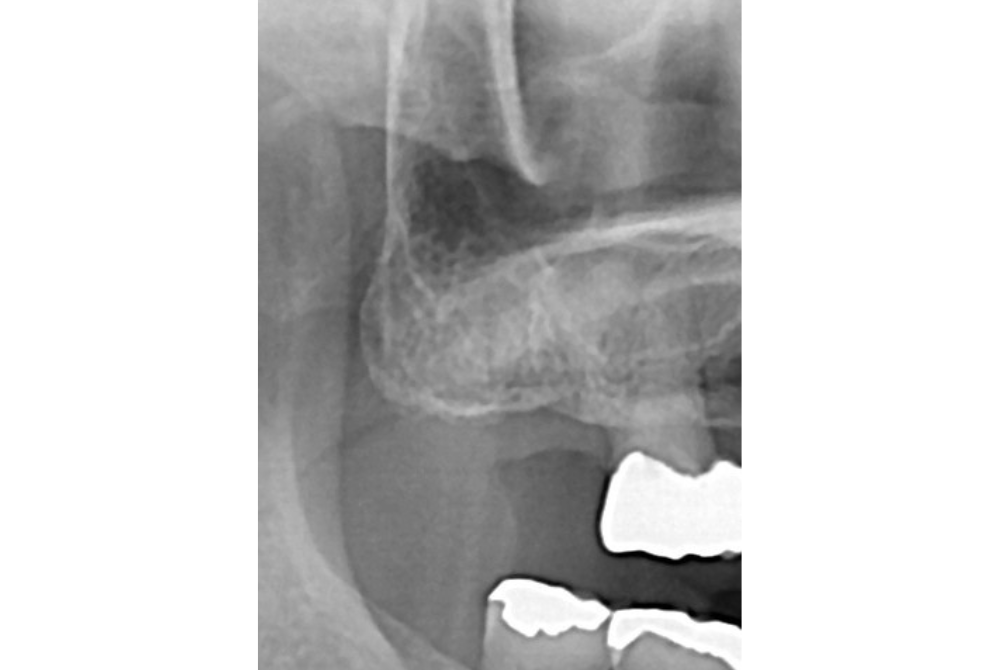

治療前

| 治療内容 | ・患者の症状:歯根破折により抜歯済みの歯にインプラントを埋入 ・治療方法 :CT及びパントモレントゲンからインプラントの埋入位置を計測。麻酔下にてインプラント植立。仮歯を入れて5か月待機。セレック治療にてジルコニアクラウンを製作、同日装着。 ・治療結果 :噛める歯が増えて、噛みやすくなる。 |